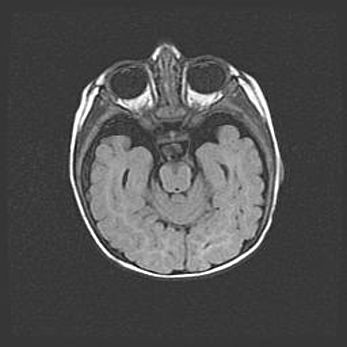

Сообщающаяся гидроцефалия. Кистозная энцефаломаляция головного мозга.

Возраст: 3 месяца 4 дня

Вес: 3100 г

Пол: женский

Окружность головы: 34 см

Срок гестации: 31 неделя

Кистозная энцефаломаляция головного мозга - одна из форм поражения головного мозга в детском возрасте. Характеризуется возникновением множественных и распространённых кист в коре, белом веществе и подкорковых образованиях головного мозга у плодов, новорождённых и детей раннего возраста. Развитие кистозной энцефаломаляции связано с внутриутробной асфиксией и гипотонией, родовой травмой, тромбозом синусов, пороками развития сосудов, инфекциями, сепсисом и другими причинами. Наиболее значимые инфекционные агенты: вирусы простого герпеса, цитомегалии, краснухи, токсоплазмы, энтеробактерии, золотистый стафилококк и другие.